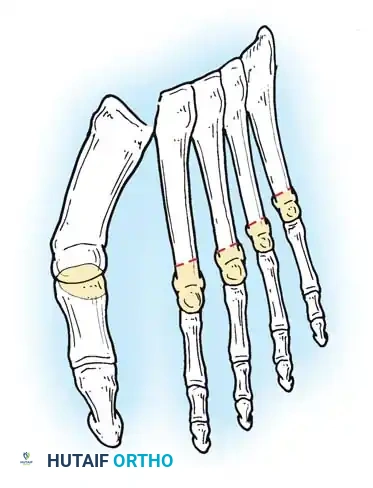

Surgical Diagrams demonstrating the principles of first MTP arthrodesis and lesser metatarsal head resection to restore a functional, plantigrade forefoot cascade.

Step 3: Lesser Metatarsal Head Resection

- Osteotomy: An oscillating saw is used to resect the metatarsal heads at the anatomical neck. It is imperative to create a smooth, parabolic cascade (the 2nd metatarsal should be the longest, tapering down to the 5th).

Fig. 81-9 (A, B) Radiographic evidence of bony proliferation at the distal end of the resected metatarsals. This remodeling can lead to recurrent plantar pressure and necessitates adequate initial resection.

Common long-term objective recurrences include:

1. Recurrence of hallux valgus (if arthrodesis was not performed or failed).

2. Dorsal posturing of the lesser phalanges on the metatarsal remnants.

3. Bony proliferation (osteophyte formation) on the distal ends of the resected metatarsals, leading to recurrent plantar keratoses.